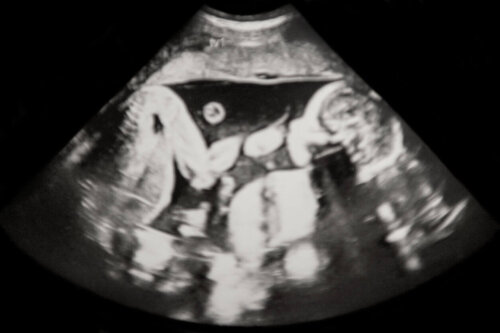

Der anvendes ultralyd til at bestemme typen af flerfoldsgraviditet, og der er to typer:

Ved flerfoldsgraviditeter kan der undfanges tveæggede eller enæggede tvillinger, hvilket kan vurderes ved ultralydsundersøgelsen.